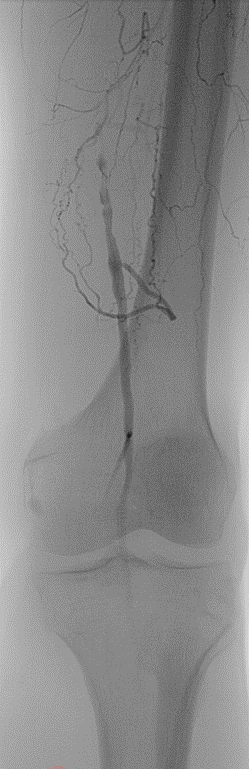

★ Case 1

noproximal stump in SFA,>250mm

★ Case 2

significantdistal collaterals